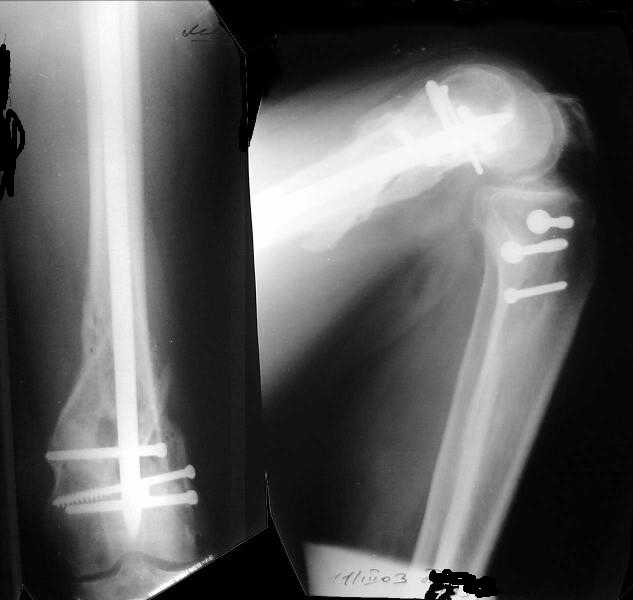

1

Sorry but I've just prepared postop images - attached. A solid 13 mm nail was used. A few degrees of recurvation appears to be which i missed on image intensifier. I'm still uncertain about

advantages/disadvantages of ante/retrograde nailing for such fractures.

Отправитель: V.M.Iyer 27 Декабрь 2003, 21:36

The fixation as you have done is excellent. The locking screws on either side of the # are so apart. When we put in a supracondylar nail thro a keyhole incison in the knee, the locking bolts will be nearer the # and will be more stable allowing him to bear wt early. That was the reason the supracondylar nail was innovated. The locking is done by jig and no freehand method saving time.